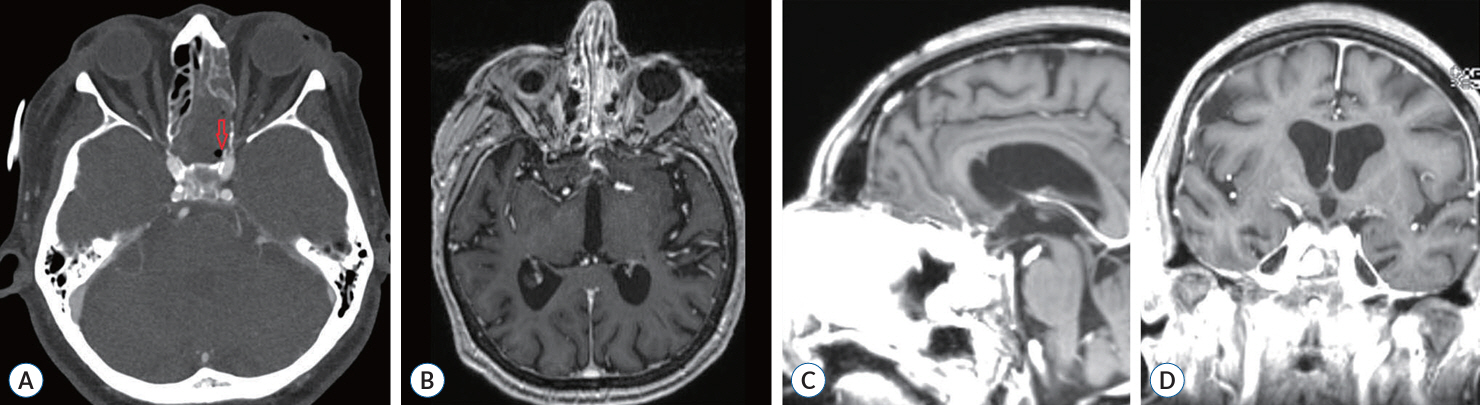

A Successful Control of the Intraoperative Bleeding from McConnell’s Artery during Fully Endoscopic Resection of Planum Sphenoidale Meningioma Using Bone Chip and Bioglue : A Case Report

- The endoscopic transsphenoidal approach is a common approach used in skull base neurosurgery to reach the sellar region. One of the intraoperative risks of this approach is intraoperative bleeding out of the carotid artery. Gentle drilling can prevent carotid artery injury. However, injury to smaller branches, such as the McConnell’s capsular artery, which is located within the surgical corridor, is more difficult to prevent. If such an injury is within the junction to the main trunk of the carotid artery, there will be a small circular defect in this area. This can result in massive blood loss and should be closed surgically immediately. We describe a clinical case of intraoperative bleeding from the McConnell’s artery originating from the carotid arterial segment (C4) in a 78-year-old female patient operated on for planum sphenoidale meningioma via endoscopic transsphenoidal approach, as well as provide a technical note on a possible technique for bleeding control in such cases. Pinpoint carotid bleeding as a result of intraoperative injury can be stopped by wedging a bone fragment in the carotid canal and fixing it in that position with histoacryl glue at the defect site.